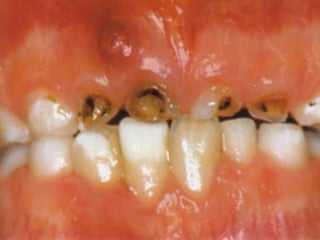

3, 4, 5 años con

cualquier evidencia

de caries en

superficie lisa de

incisivo central

Cantidad total de

superficies afectadas es

≥de 4 a los 3 años, 5 a los 4

y 6 a los 5

De esta forma se enfatiza la

seriedad de la condición